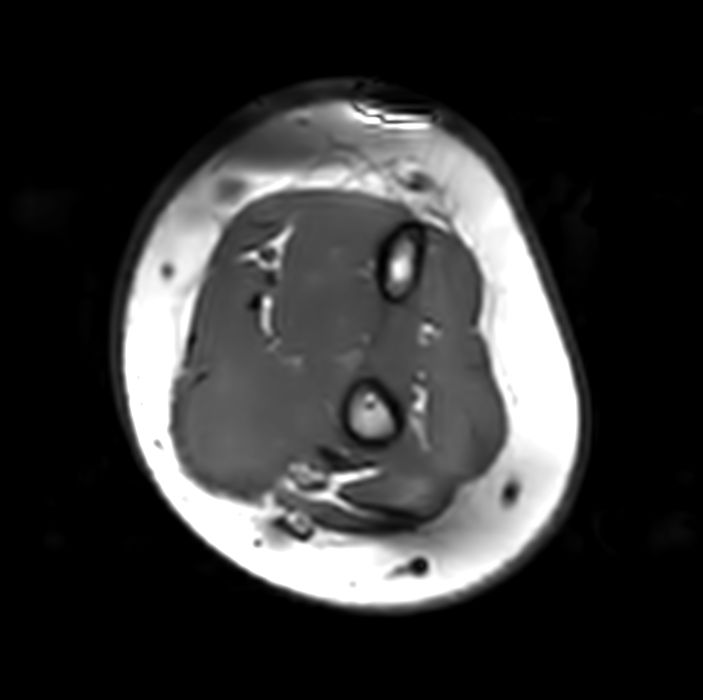

Pediatric forearm with lesion

Pediatric patient with a lesion in the forearm. mDIXON XD provides uniform fat-free imaging and allows for multiple image types in one single scan. Integration of Compressed SENSE acceleration technique enables speeding up of the entire exam.

Axial T1w FatSat +gadoCompressed SENSE